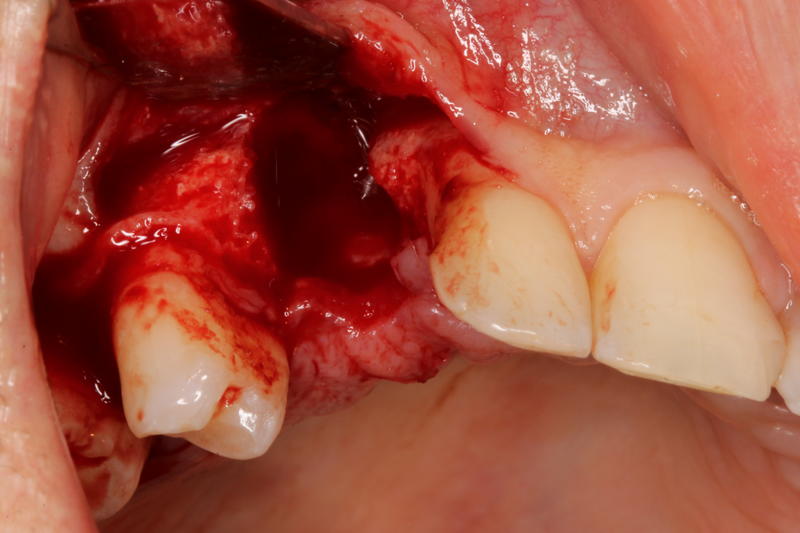

How to handle the infection?

Learn the steps to not only remove the infected implant, but also rebuild the site